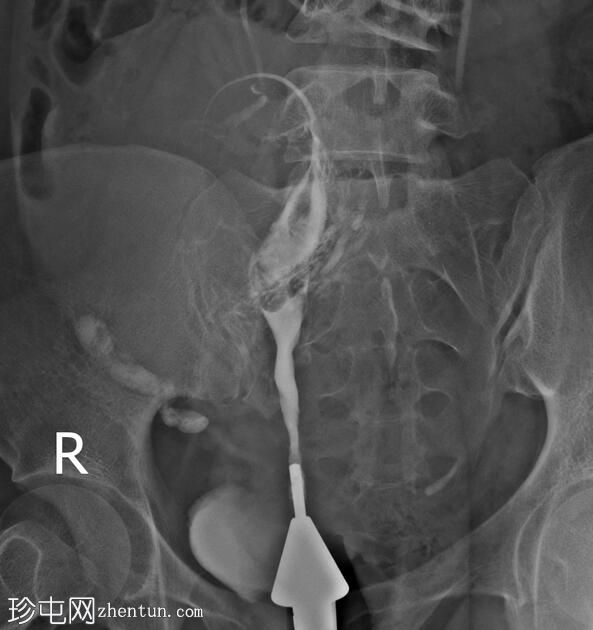

注射更多造影剂后,造影剂渗入子宫肌层静脉和右侧性腺静脉,随后进入肾静脉。

手术开始三分钟后,造影剂进入肾脏,充盈肾盂肾盏系统,然后流入输尿管和膀胱,形成类似于静脉肾盂造影(IVP)的影像